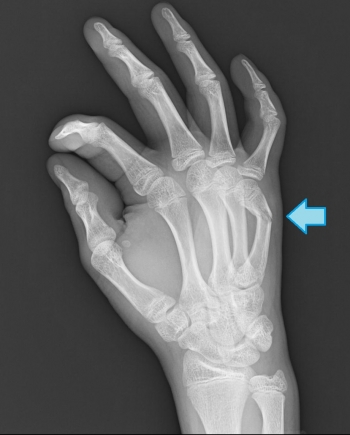

今日、ご紹介するのは、手指骨骨折の分類の詳細についてご紹介していきたいと思います。

手指骨折の分類

基節骨骨折

①骨幹部骨折 ②骨頭・頚部骨折 ③基底部骨折

中節骨

①頚部骨折 ②骨幹部骨折

末節骨骨折

①マレットフィンガー

比較的頻度の高い骨折です。

完全骨折の場合は、しばしば定型的な掌側凸変形になる。

スポーツによる過伸展や過屈曲による損傷が多い。

骨幹部骨折

近位骨片は虫様筋や骨間筋により屈曲、遠位骨片は背側腱膜により掌側凸に転位する。

骨頭・頚部骨折

頻度としては高くないですが見逃されやすく、小児に多い骨折

骨折した骨頭部は、骨折端を掌側に向けて90°回転し、側副靭帯により絞扼されて整復が困難。

基底部骨折

掌側凸の変形を呈す。

小児には骨端線離開を見ることもある。